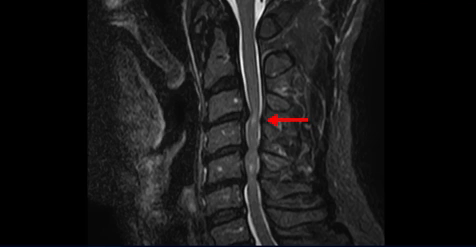

젓가락질과 단추 끼우기가 어렵고 걸으면 발을 헛딛는 경추척수증 환자분의 MRI 상태 및 증상은?

이 환자분은 목디스크 3, 4번의 심한 디스크로 인해 경추척수증이 발생한 환자입니다. MRI에서 보시다시피 심하게 밀려 나온 목 디스크로 인해 척수신경이 눌려서 신경이 손상된 게 하얗게 보입니다.

경추척수증이란 중추신경인 척수가 목디스크나 골화된 후종인대 또는 경추 협착에 의해 심하게 눌려서 손상이 생기는 질환입니다. 이 환자분의 증상은 목이 항상 담 걸린 듯 뻐근하고 걸을 때 발을 헛딛고 젓가락질이 잘 안되며 단추를 끼울 때 잘 안 껴지고 손에 잡은 물건이 자꾸 떨어지려고 하는 상태였습니다. 이는 전형적인 경추척수증의 증상입니다.

그런데 이 경추척수증은 수술 없이도 재활 치료를 통해 좋아질 가능성이 있습니다. 특히 척수증의 원인 중에서도 목디스크로 인한 경추척수증이 수술 없이 회복될 가능성이 제일 높습니다. 경추척수증은 척수가 물리적으로 압박을 받고 있기 때문에 목 주변의 여러 근육, 예를 들면 사각근, 흉쇄유돌근 등과 같은 목 앞쪽 근육들 그리고 승모근, 판상근 등과 같은 목 뒤쪽 근육들. 즉, 목 주변에서 척수에 압력을 주고 있는 뭉친 근육들을 잘 풀어주고 재활치료 해주면 물리적 압박이 줄어들면서 증상이 호전되는 경우가 있습니다.

또한 대부분의 척수증 환자가 거북목과 굽은 등을 가지고 있는데 이런 환자분들의 일자목 또는 역 c자형 목커브는 척수에 더 많은 압력을 줍니다. 그래서 가슴 근육과 어깨 근육, 등근육을 치료하여 거북목과 굽은등을 교정해주면 목의 커브가 좋아지면서 척수에 대한 압력이 줄어드는데 도움을 줍니다.